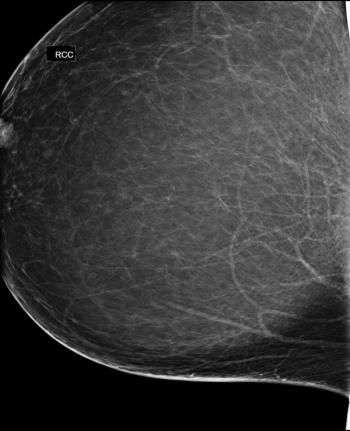

45-year-old female with abnormality on routine screening mammogram, underwent breast reduction surgery 2 years prior.